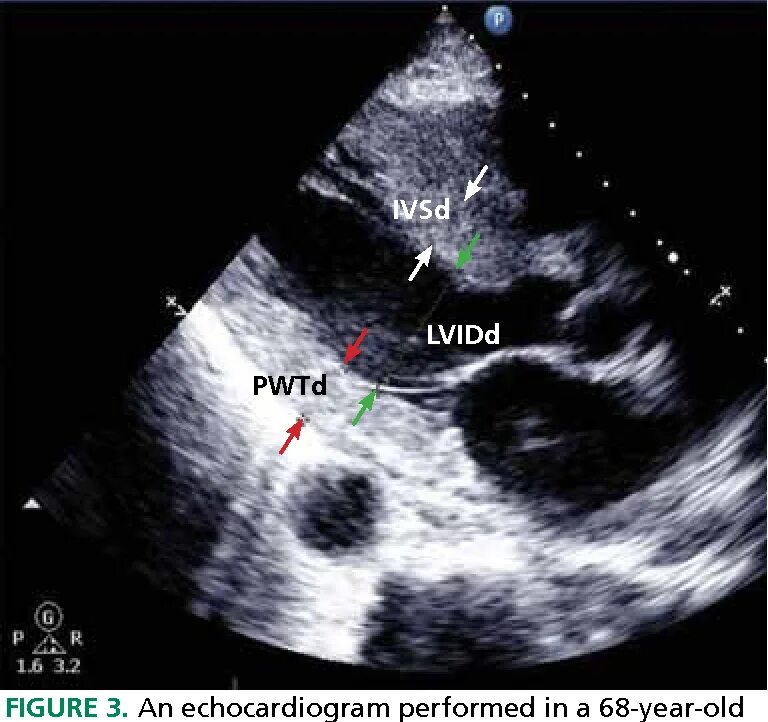

Ддлж по 1 типу по узи